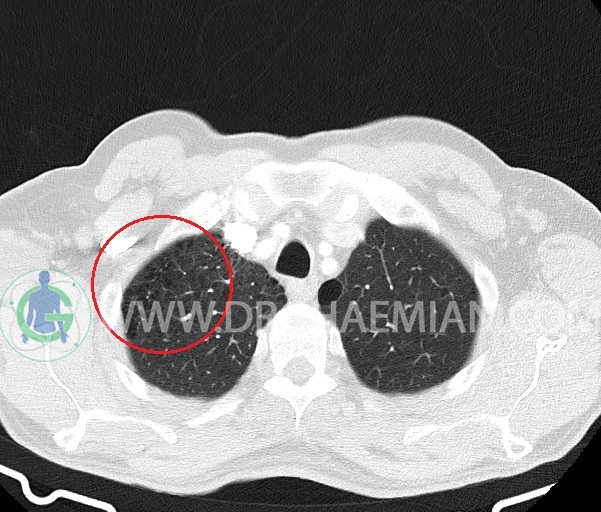

– آمفیزم سنتری لوبولار در لوب فوقانی هر دو سمت با ارجحیت در سمت راست

–آمفیزم پاراسپتال در هر دو ریه

– ندول پری فیشرال به سایز 6mm در فیشر مینور راست (بدون اهمیت بالینی )